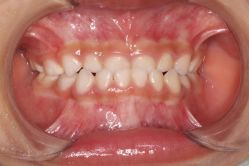

• 青苗儿童口腔(长楹天街购物中心)

• -青苗儿童口腔(长楹天街购物中心)

会员1407914 上传于 20-09-21 | 报错

晔子_6763 上传于 20-09-20 | 报错